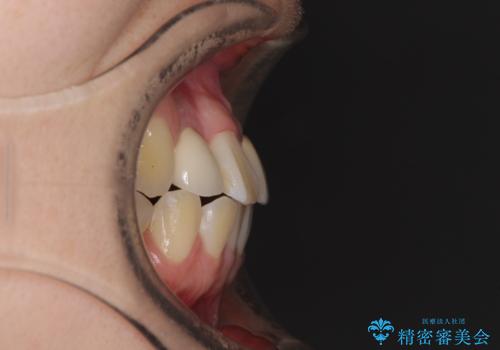

- 奥歯が痛いとのことで来院された患者様です。

上顎親知らず周辺の炎症と、神経組織の失活した歯の炎症による痛みが認められたため、親知らずの抜歯と根管治療を行いました。

根管治療を行った歯はクラウンによる補綴治療が必要となりますが、高校生の頃に行った矯正治療の後戻りも気になるとのことで、補綴治療を行う前に矯正治療を行うこととしました。

後戻りは軽度であり、インビザラインにて歯列を整え、その後にオールセラミッククラウンにて補綴治療を行うこととしました。